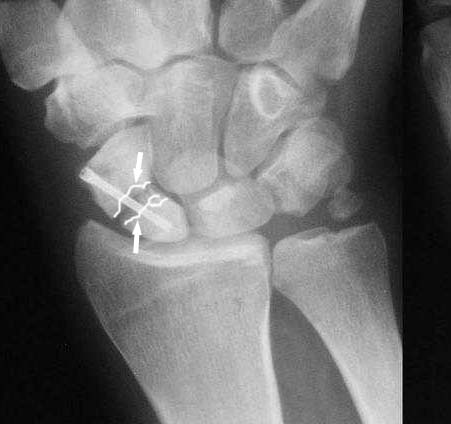

Ув. Данил! По моему мнению все-таки ложный сустав -склероз отломков (приложение), 5 мес, диастаз. Для подтверждения можно выполнить КТ кистевого сустава (формирование замыкательной пластинки, склероз концов отломков и т.д.,), а так же по КТ можно выявить сохраняется ли подвывих каких-либо костей запястья или нет. При наличии ложного сустава целесообразно будет удалить винт,обработать концы отломков, разрушив замыкательные пластинки и выполнить остеосинтез ладьевидной кости винтом с костной аутопластикой зоны псевдоартроза (либо гидроксиаппатитом...) Гипс 1,5 мес мин. Снимков найти сейчас не получилось. позже дошлю.

Такое ощущение, что имеющееся состояние ещё не является необратимым (отсутствие склероза отломков на уровне перелома) и обусловлено исключительно нестабильностью (сам винт оказался слабоват или чрезмерные нагрузки привели к срыву фиксации - пациент, заметьте, мотоциклист!)

I am not sure if the differential of a nonunion vs. pseudoarthrosis means much in this context. The distal pole of the screw has a lucency, so the

nonunion is most likely unstable and moving. It needs revision. The radial styloid does not have evidence of DJD, so I do not think it needs to be resected. The surgery will probably require an open revision, removal of necrotic bone and soft tissue interposition, and would benefit from some